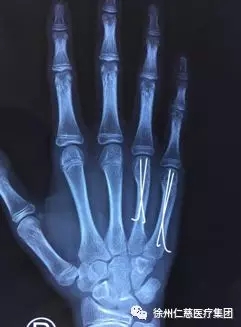

术后六周复查X线片

术中,熊祖国医生将克氏针尾端避开指伸肌腱,放置于皮下贴掌骨位置,术后皮肤无疤痕,术后六周骨折愈合良好。

病情:15岁的小翔(化名)前阵子用右手拳击桌子后,导致4、5掌骨颈骨折,骨折掌侧成角移位、掌骨头塌陷。